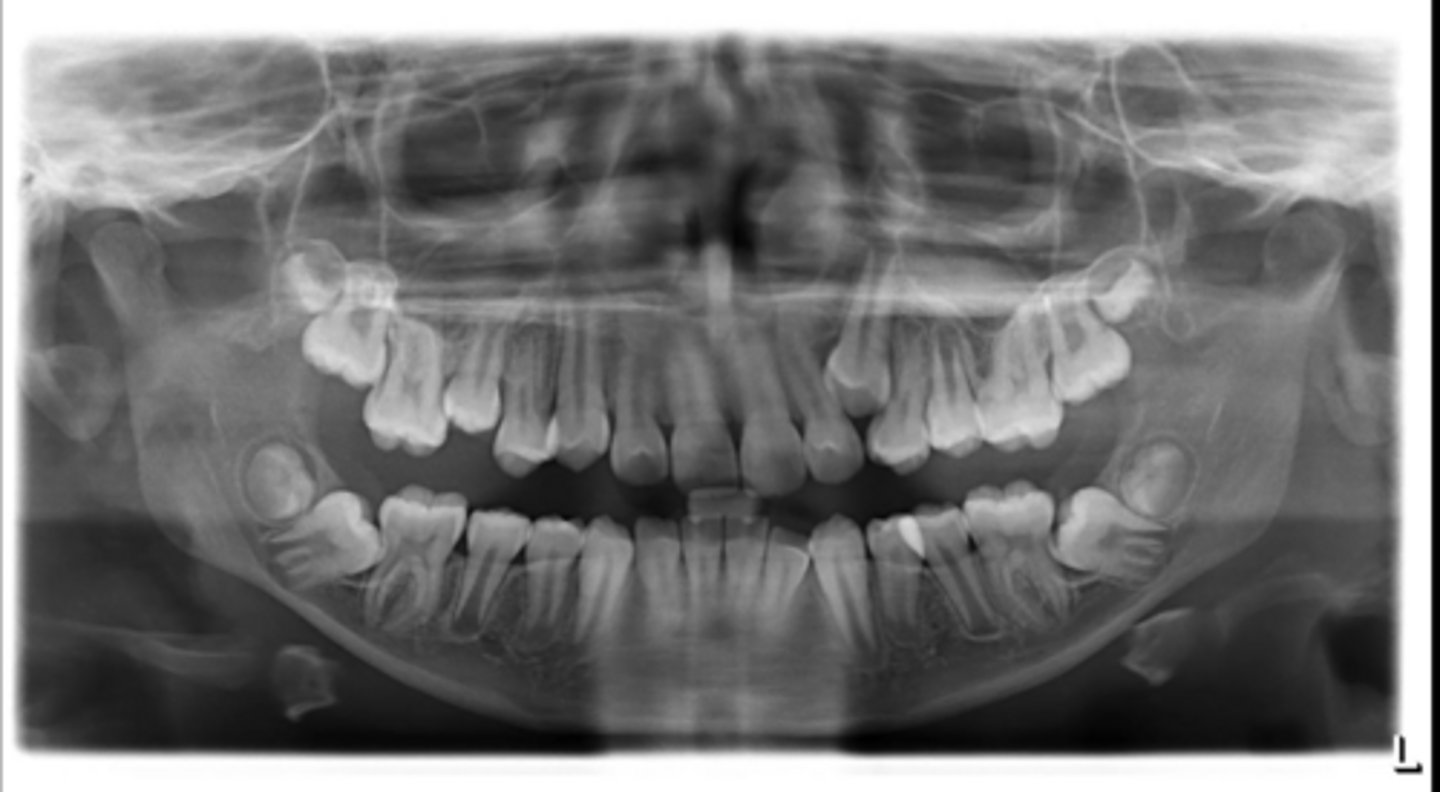

Yes - #2, also #27?

Dilacerated roots?

No

Are there congenitally missing teeth in the maxillary arch?

Are there congentially missing teeth in the mandibular arch?

Any supernumerary teeth?

Yes - mandibular second molars

Any impacted teeth?

Yes

Are the condyles symmetrical?

Maybe in the upper molars

Are there any dilacerated roots?

Are there congenitally missing teeth in the mandibular arch?

Are there any supernumerary teeth?

Are there retained primary teeth?

A little bit

Is there crowding?

Is there any pathology?

Possibly #20